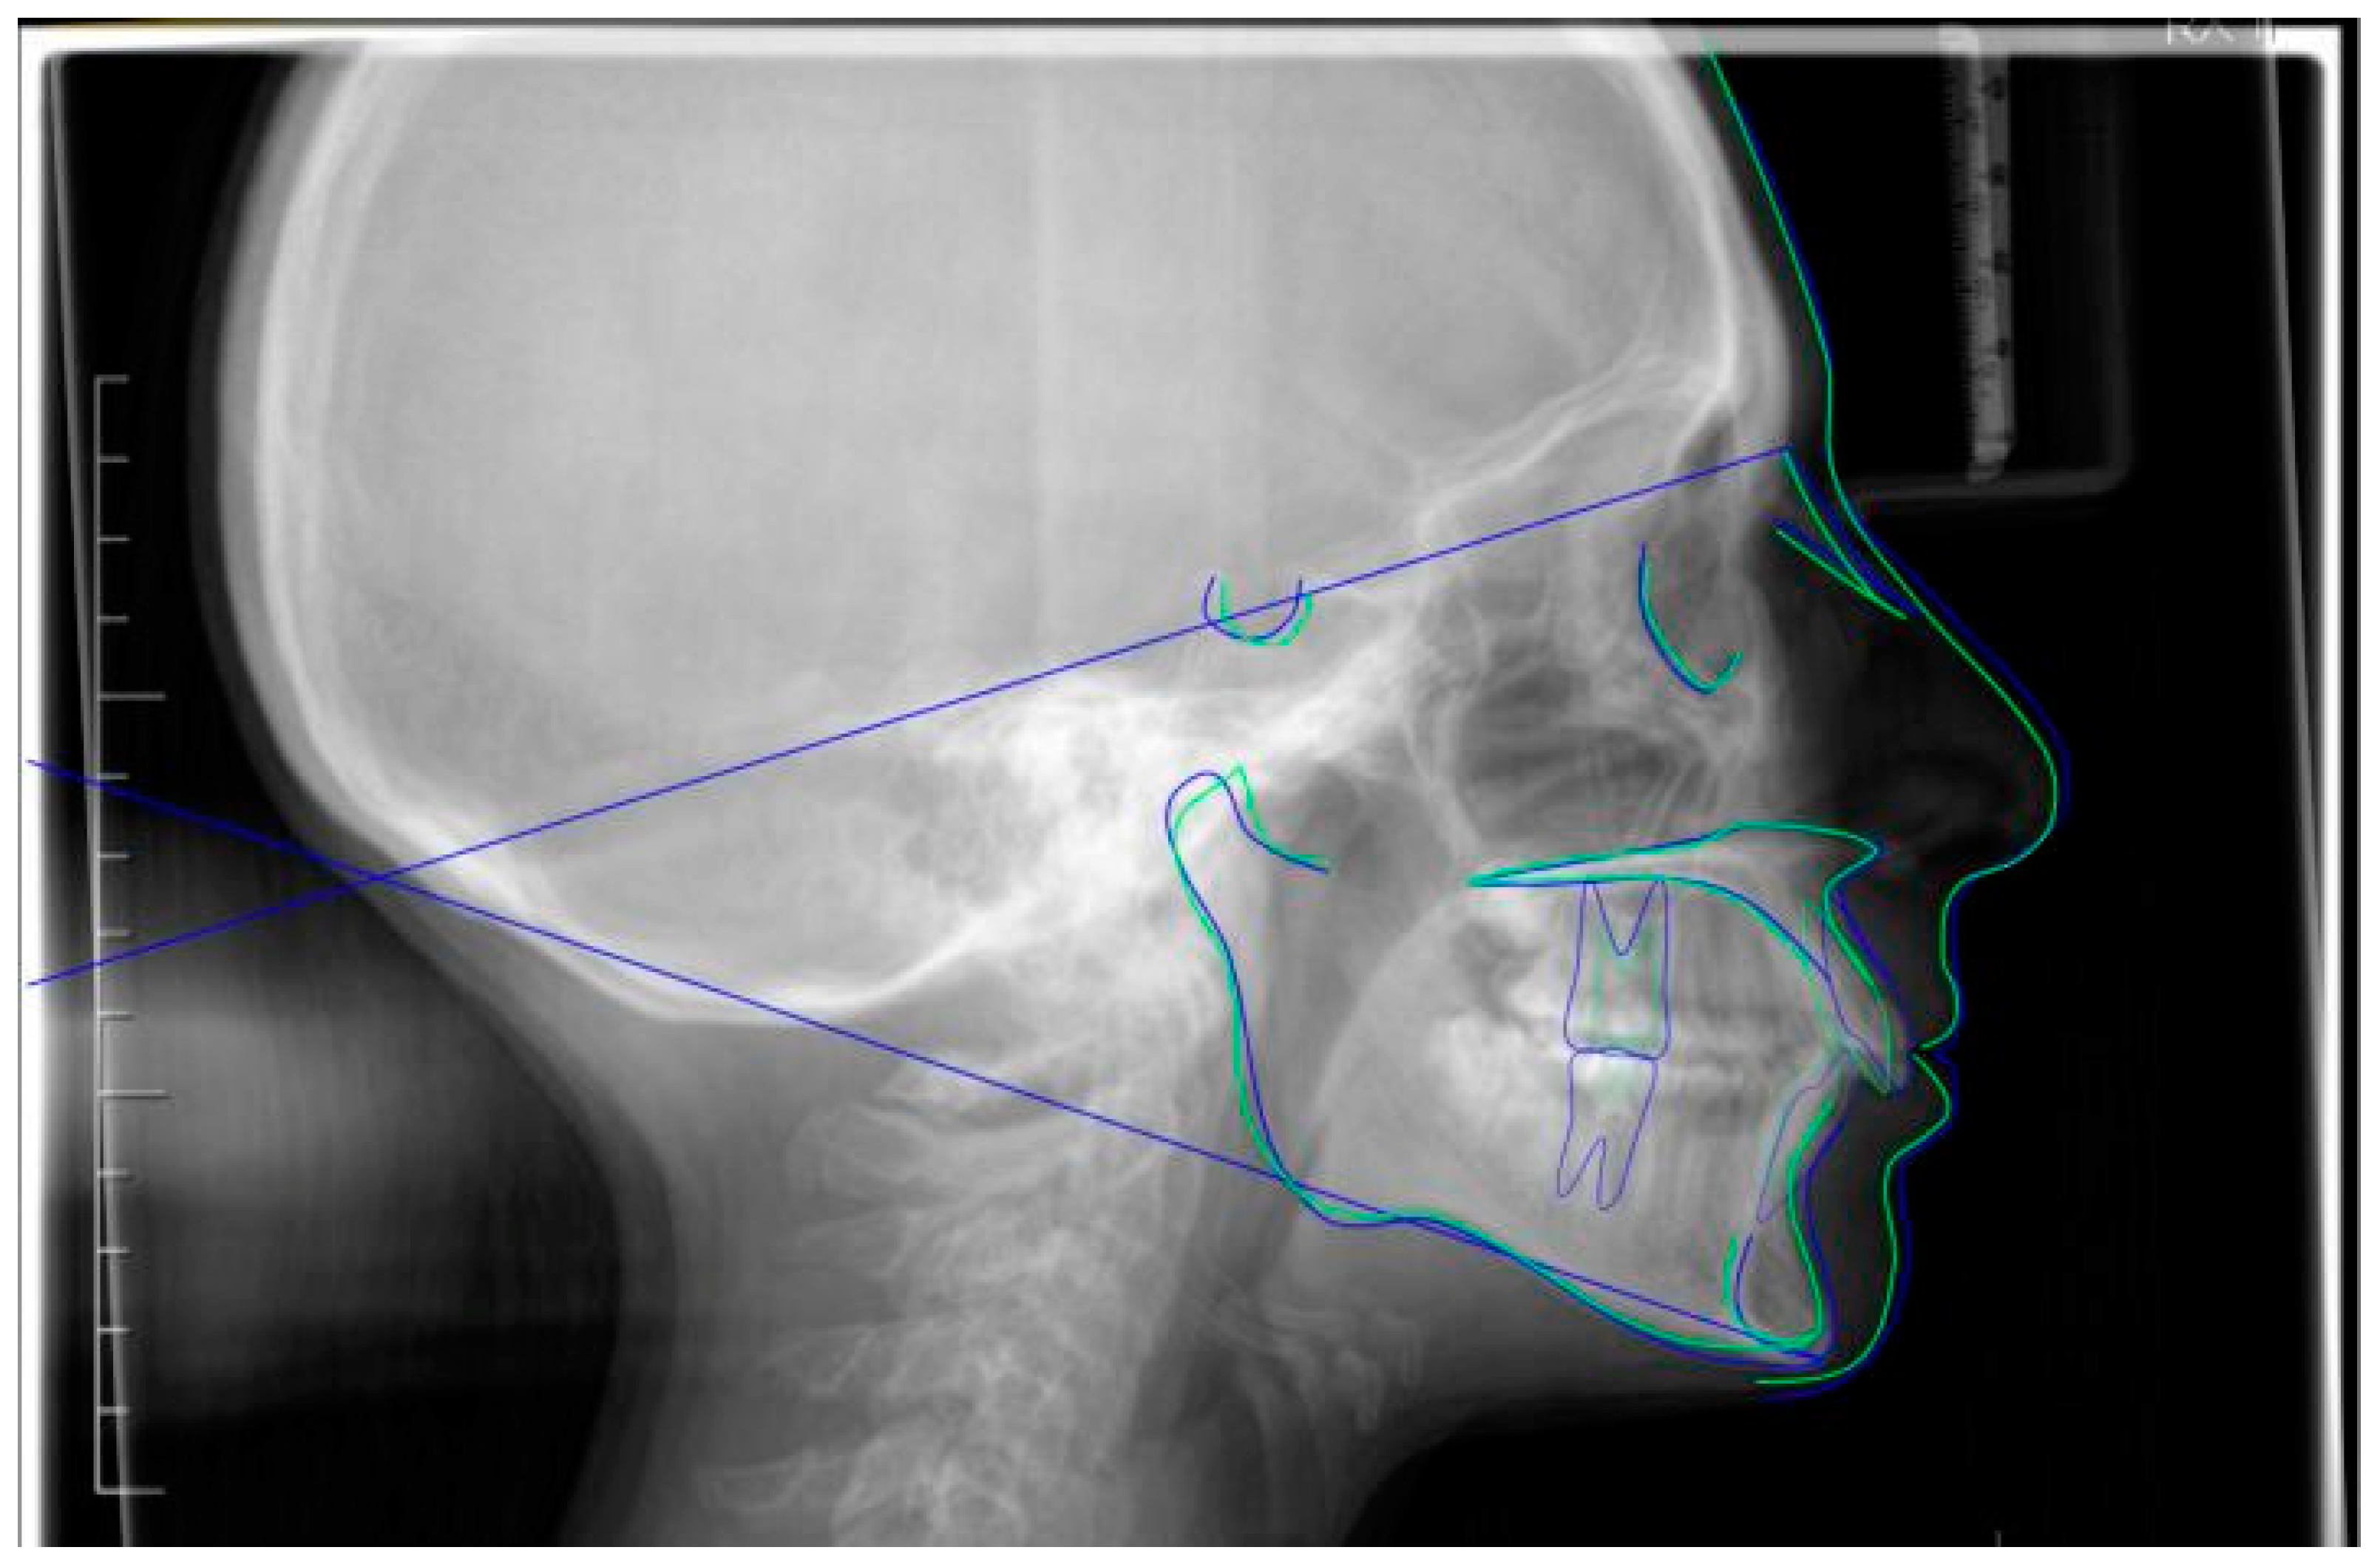

Figure 2.

Pre-treatment lateral teleradiography.

A case of CA therapy without attachments and without the aid of hybrid elements has been documented. The patient, an 18-year-old woman at the beginning of treatment (October 2021), signed written informed consent to orthodontic treatment and authorized the use of her anonymized treatment data, including photos, X-rays and virtual models of the dental arches. She needed to rehabilitate two edentulous areas corresponding to first maxillary and mandibular molars, both on the left side, assessed as irrecoverable for destructive caries at the time of the orthodontic evaluation (Figure 1). The patient refused rehabilitation with prosthetic implants and orthodontic treatments with fixed or hybrid fixed-removable therapy. Orthopanoramic (Figure 1) and lateral teleradiography of the skull (Figure 2) were acquired to make the necessary assessments. The cephalometric examination was performed using the Cephio© Cephalometric Analysis artificial intelligence driven platform (Cephio sp. z. o. o. [Ltd.]). Her skeletal class II malocclusion was due to maxillar and mandibular retrusion (SNA 80°, SNB° 74.6°, ANB 5.4°, SNPog 76.2°). She had “long face” (OP-SNP 21.1°), a posterior inclination of the jaw (MPGoGn- SNP 35.4°), slight hyperdivergence (FMA 26.2°), with pro-inclined lower incisors (1-NB 28.4°, IMPA 96.1°) and retroclined upper incisors (1-NA 14.1°, FMIA 57.7°). Overjet and overbite were severely altered (6 and 7 mm) (Table 3). Orthodontic treatment started 4 months after the first left maxillary and mandibular molar extractions. Intraoral and facial photos were captured (Canon© Coolpix A900, Canon, Tokyo 146-8501, Japan). Dentally, she had a first molar and canine class on the right side, and a first canine class on the left side in which the molar class was no longer assessable (initially it was a first class); however, a partial reduction in edentulous spaces was observed due to the movement of adjacent teeth (Figure 3) and lower incisors were moderately crowded. Precision silicone impressions (Elite HD+ Putty Soft Normal and Elite HD+ Super Light Body, Zhermack SpA, Badia, Italy) were taken using the double technique. Then, a virtual setup of the treatment with CAs was developed to evaluate its feasibility. It showed full closure of edentulous spaces and was also discussed successively with the patient. The orthodontist clarified there were no data from the literature (at that time) to support the successful movements required with only CAs. The orthodontist and patient started treatment by agreement. The informed consent to treatment was signed. It also covered clinical re-evaluation with solutions less favorable to the patient’s preferences if the results in the middle of treatment had been clinically unsatisfactory or unfavorable. The orthodontist explained the need to intercept any treatment complications to the patient. This also related to the predictability of intermediate results for medico-legal reasons, for the mutual protection of her as a patient and of the orthodontist as a professional responsible for the therapy. Initial and final virtual models were superimposed to evaluate the movements obtained (Maestro 3D©, AGE Solutions S.r.l., Pontedera- Pisa, Italy). At the end of the therapy, new X-rays were requested and new intraoral and extraoral photos were recorded.

Post-treatment lateral teleradiography.

Figure 9.

Superimposition of pre- (blue) and post- (green) cephalometric traces (reference plane SN) with appropriate function on the Cephio platform.